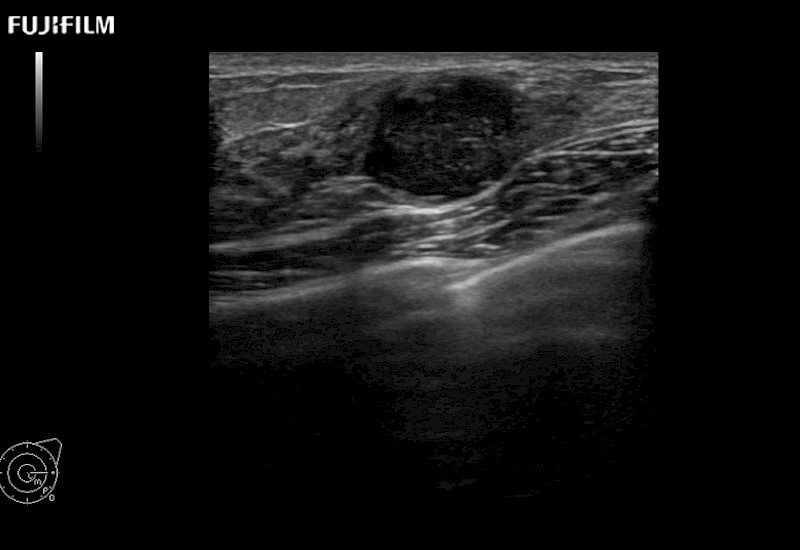

Our dedication to Surgical Oncology allows us to offer superior image quality, outstanding system reliability and intuitive use of cutting edge technology.